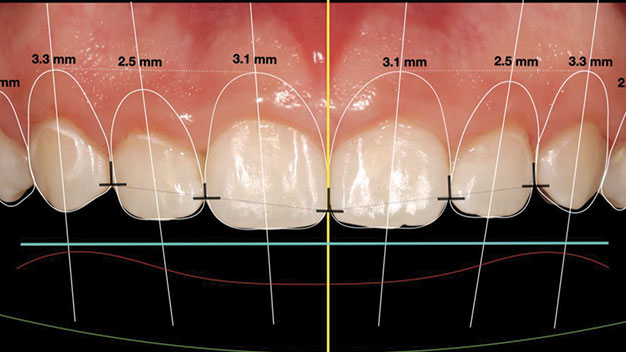

Edentulism in the posterior maxillary region presents a challenging scenario for dental implant rehabilitation due to vertical ridge dimension bone loss and the close proximity to the floor of the maxillary sinus. In addition, alveolar ridge width loss and thinning of mucosa is a common clinical scenario in areas of long term tooth loss. To … Read more